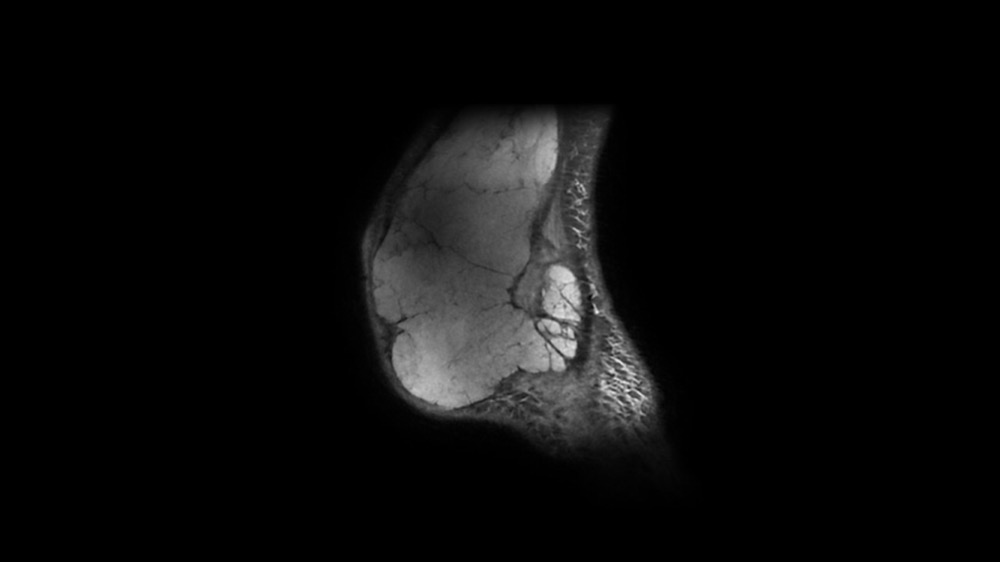

Bone Club

Bernard Hollier 18/05/2022